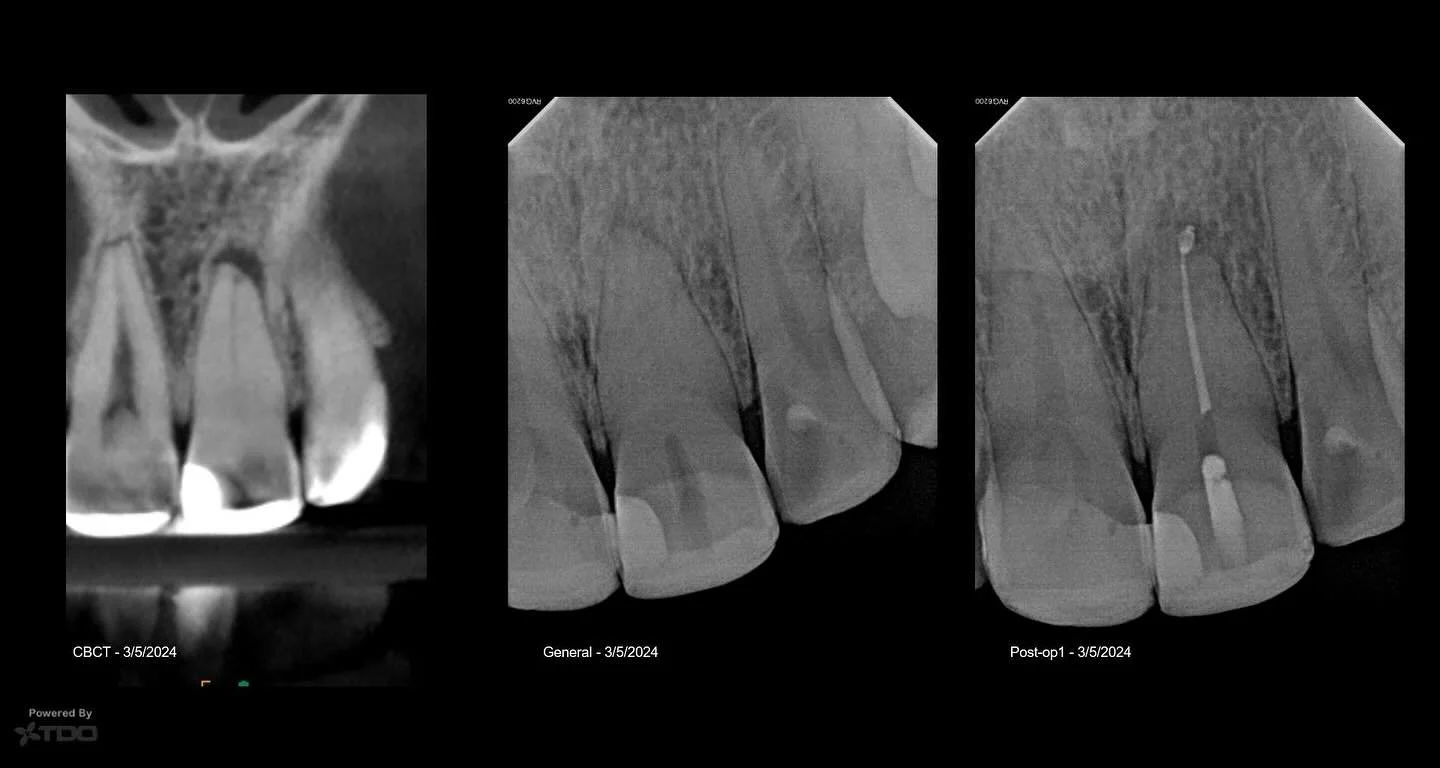

I am a board-certified endodontist with advanced specialty training and an academic interest in diagnostic reasoning, retreatment, and microsurgical endodontics. My work emphasizes CBCT-guided decision-making, interdisciplinary collaboration, and evidence-based care in complex clinical scenarios.